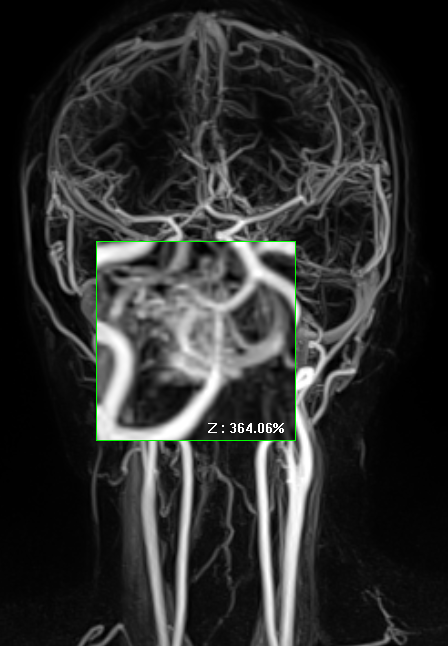

조영증강 CT나 CTA(CT angiography)을 시행하면 “뒤엉킨 벌레뭉치(bag of worms)” 같은 특징적 조영 패턴 나타난다.